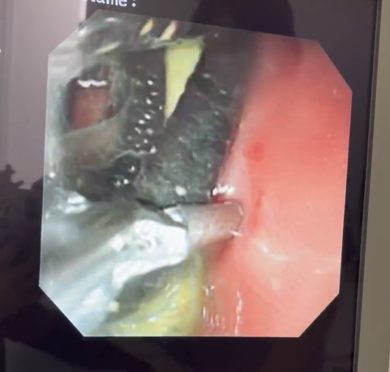

まず初めに内視鏡で観察したところ胃の中に黒いヒモ状のものがたくさん見られやはり異物が原因であったことがわかりました。しかしそのヒモの量が多く、太いことから内視鏡で摘出できず開腹手術に切り替えました。

幸い、異物は胃の中に留まっていたため胃の一部を切開し摘出しました。

黒い髪ゴムのようなものが何本かとビニールのようなものも一緒に出てきました。